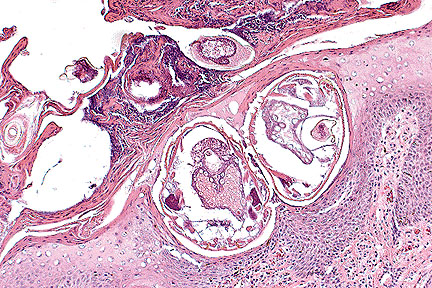

Cross sections of two intraepidermal acarids from the pinna of a fox. (HE, 200X, 122K)

Morphologic Diagnosis: Auricular dermatitis, with marked purulent and hyperkeratotic epidermitis and associated mange parasites, chronic, severe.

Etiology: Sarcoptes scabiei

AFIP Diagnosis: Ear: Dermatitis, plasmacytic, chronic, diffuse, moderate, with severe orthokeratotic and parakeratotic hyperkeratosis, intracorneal abscesses, epidermal hyperplasia, and numerous intracorneal acarid parasites, red fox (Vulpes vulpes), canid, etiology consistent with Sarcoptes scabiei.

Conference Note: This case was reviewed by Dr. C.H. Gardiner, parasitology consultant for the Department of Veterinary Pathology, AFIP. Sarcoptes scabiei is the cause of scabies in humans and sarcoptic mange in most domestic animals; each variety of mite is named for its host, for example Sarcoptes scabiei var. canis. The species adapted mites may infect other host species; however, in most cross-infections, the mites do not complete their life-cycle. In the normal host, the mites burrow into the stratum corneum and feed on cells of the stratum granulosum and stratum spinosum. Epidermal damage induces epithelial hyperplasia and the development of parakeratotic crusts. The females lay 40 to 50 eggs which develop into larva and then nymphs in the intracorneal burrows. Neither adults nor eggs survive well in the environment.

Transmission is predominantly by direct contact, although indirect contact with fomites is another possible mechanism. The initial lesions of sarcoptic mange are localized and nonpruritic. After a period of 7 to 11 weeks, there is a generalized urticarial eruption and extreme pruritus; these lesions coincide with the development of immediate and delayed hypersensitivity reactions. Immunosuppressed animals do not mount adequate hypersensitivity reactions and develop severe lesions with large numbers of mites. Common causes of immunosuppression in animals include malnutrition and concurrent disease; in Maryland, canine distemper is diagnosed in approximately 50% of the wild canids presenting with sarcoptic mange.

Animals infected with Sarcoptes mites develop erythematous macules and crusts on the skin. Immunosuppressed animals may develop massive infections with alopecia, lichenification, and accumulation of thick scales and fissuring of the skin. Histologically, the mites can be seen within the parakeratotic stratum corneum. The adult mites have striations on their cuticles and large dorsal cuticular spines; Sarcoptes is the only mite with these prominent dorsal spines. There is epidermal hyperplasia and an overlying thick crust composed of orthokeratotic and parakeratotic debris, serum, and viable and degenerate neutrophils. Dermal vessels are dilated and lined by hypertrophic endothelium. There is often a perivascular infiltrate of lymphocytes and eosinophils. Chronic lesions have dermal fibrosis and a predominantly mononuclear inflammatory response.